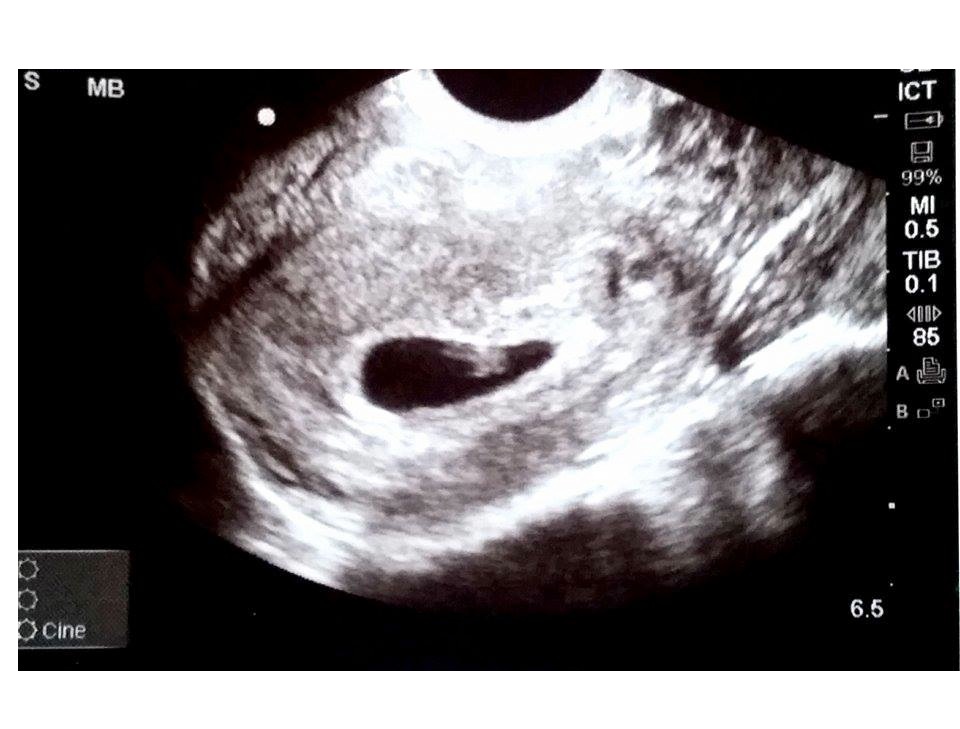

• You're totally not crazy! It was my understanding that early ultrasounds are kind of standard when there has been a miscarriage.

I personally also had an ultrasound at exactly 6w3d, but that's because I did IVF, so the fertility clinic monitors everything pretty closely. We were able to measure the heart rate and could see the yolk sac and fetal pole.

I'm attaching the ultrasound from that day :)